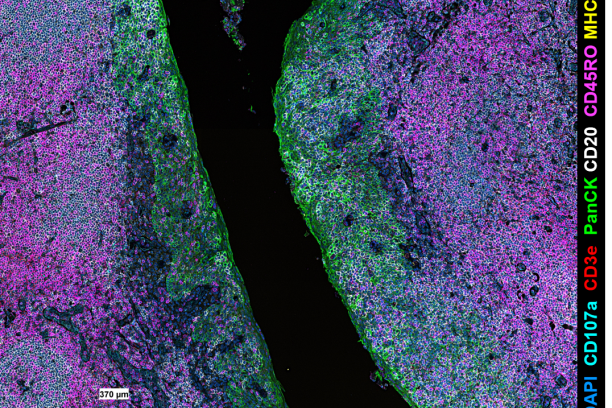

We are so excited to offer the PhenoCycler (formerly CODEX) as a new core service through the Innovative Translational Shared Resource at the Vanderbilt Ingram Cancer Center! The CODEX is a highly multiplexed immunofluorescence system that provides spatial characterization of the tissue microenvironment at the single cell level and uses single step staining to preserve tissue integrity and an automated process of imaging biomarkers using the PhenoCycler instrument and Keyence BZ-X 810 microscope.